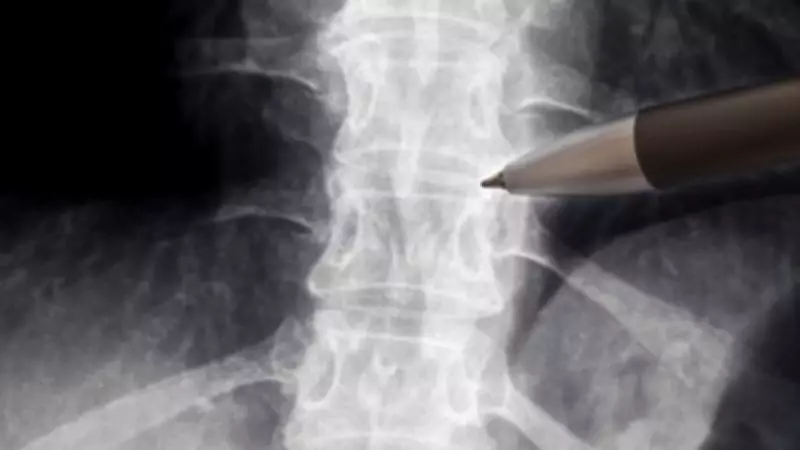

Os casos ganharam escala e visibilidade após a divulgação, no ano passado, de um estudo preliminar realizado pela Universidade Federal do Rio de Janeiro (UFRJ), liderado pela pesquisadora Tatiana Coelho de Sampaio, que envolveu oito pacientes. De acordo com os dados preliminares apresentados, dos oito pacientes que receberam a polilaminina, seis apresentaram evolução clínica, ou seja, demonstraram alguma recuperação dos movimentos.